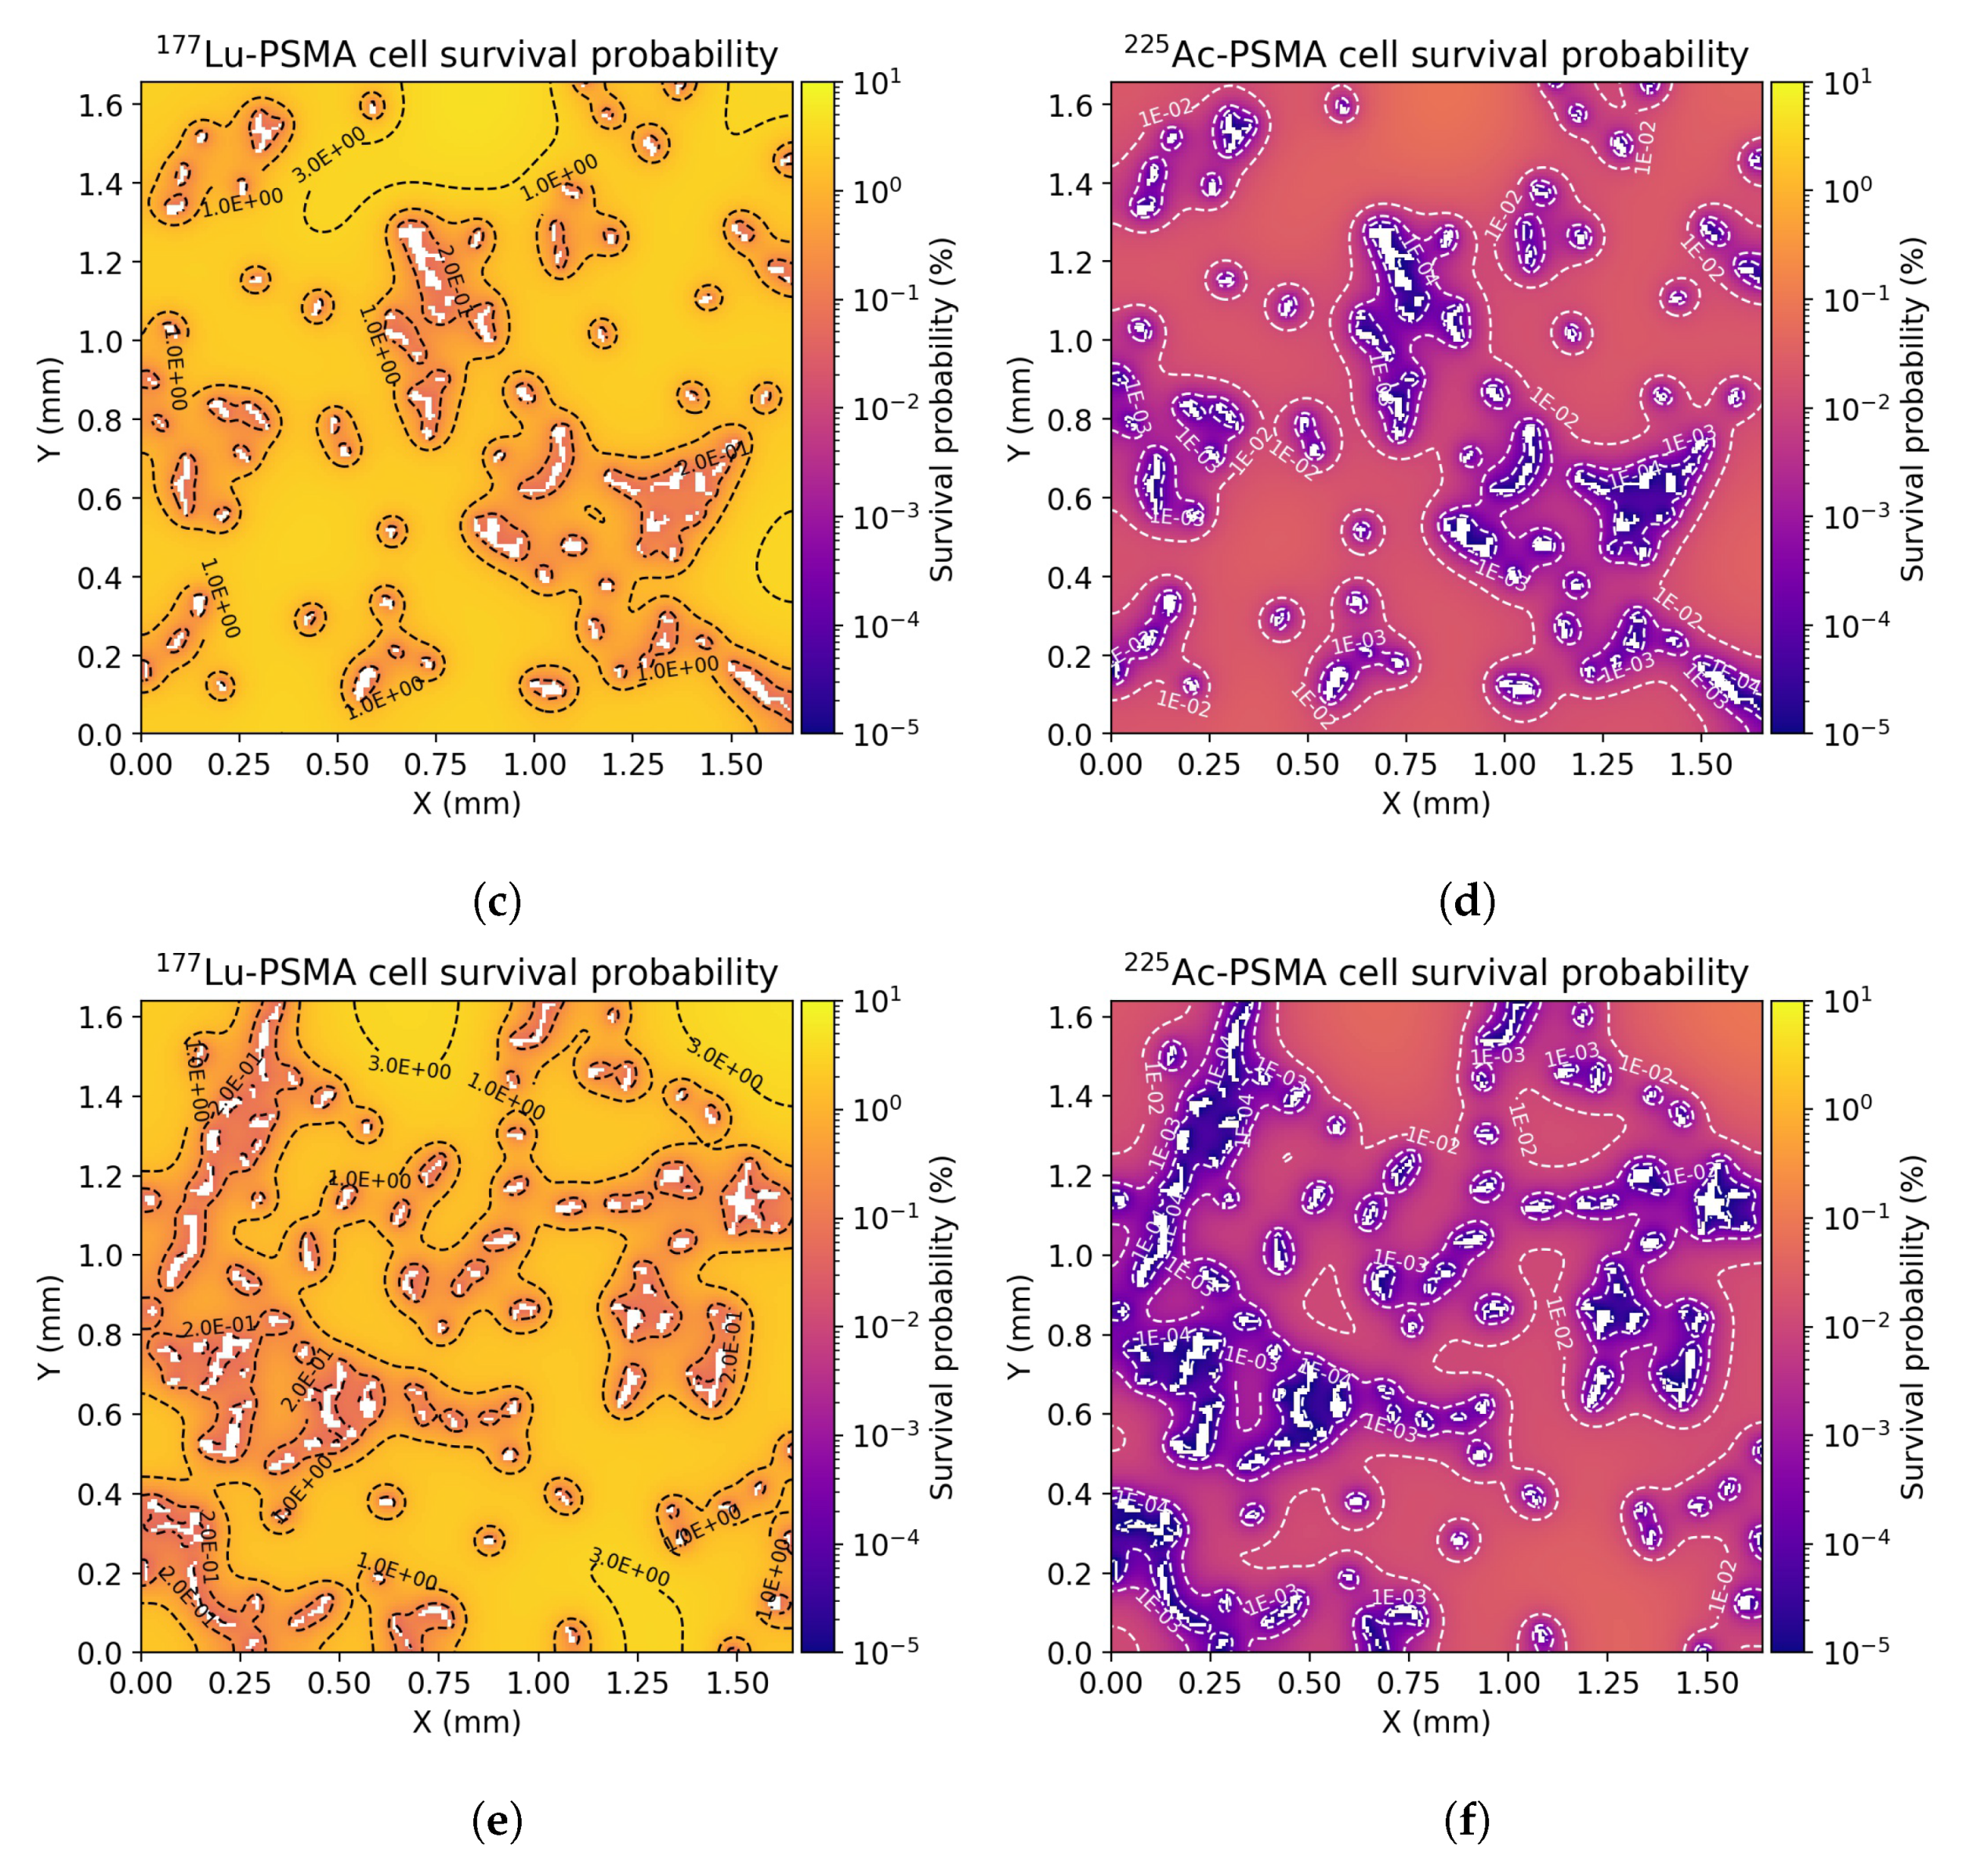

3.3. Radiobiological Efficacy Analysis